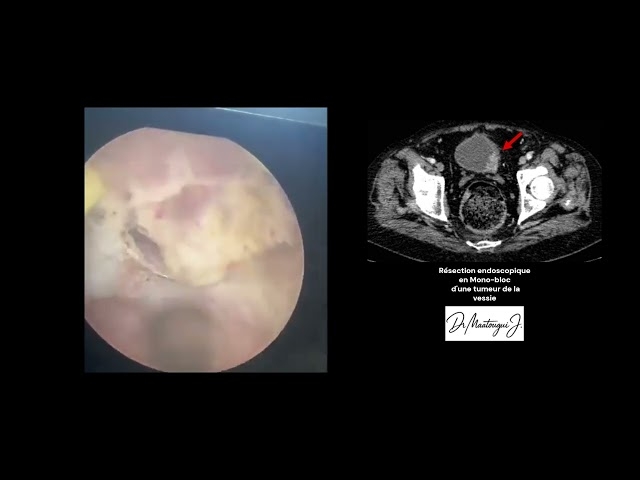

Le Dr Jasser Maatougui est un chirurgien urologue exerçant à Ben Arous. Il est spécialisé dans le diagnostic et le traitement chirurgical des affections de l’appareil urinaire et génital chez l’homme et la femme. Il pratique notamment la chirurgie des varicocèles, la résection de la prostate, le traitement des calculs urinaires au laser, la chirurgie de l’adénome prostatique, la pose de prothèses péniennes et le traitement des cancers urologiques. Le Dr Maatougui parle arabe, français et anglais, et reçoit ses patients au Centre Médical Phoenix du lundi au samedi. Les rendez-vous peuvent être pris en ligne via ce site.